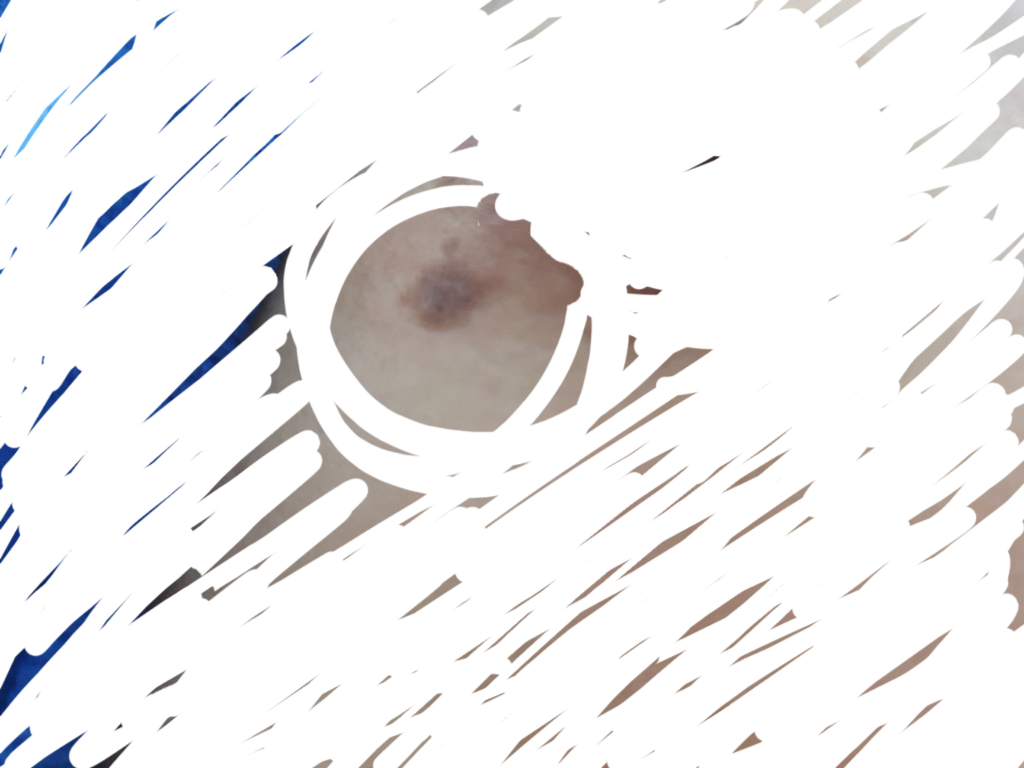

가슴에 점이 이상해요......

가슴유두 밑에 점이 자극적이고 통증이 있는 느낌이 있어요... 처음에는 가려웠는데 리도맥스같은 연고를 바르니 가라앉더라구요...브라를 압박하는 것을 입어서 자극되서 그러는지 걱정이 되네요..

무서워요..ㅠㅠ

• 1번 째 사진